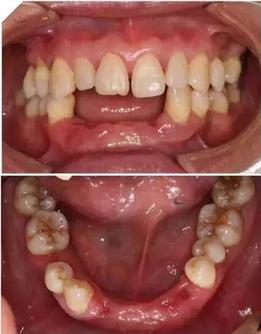

通過3shape trios口內(nèi)掃描儀掃描數(shù)據(jù)。

利用3shape導(dǎo)板軟件虛擬排牙

以修復(fù)為導(dǎo)向規(guī)劃植體

牙支持式導(dǎo)板生成

通過3Shape Dental System軟件同期設(shè)計(jì)臨時(shí)冠